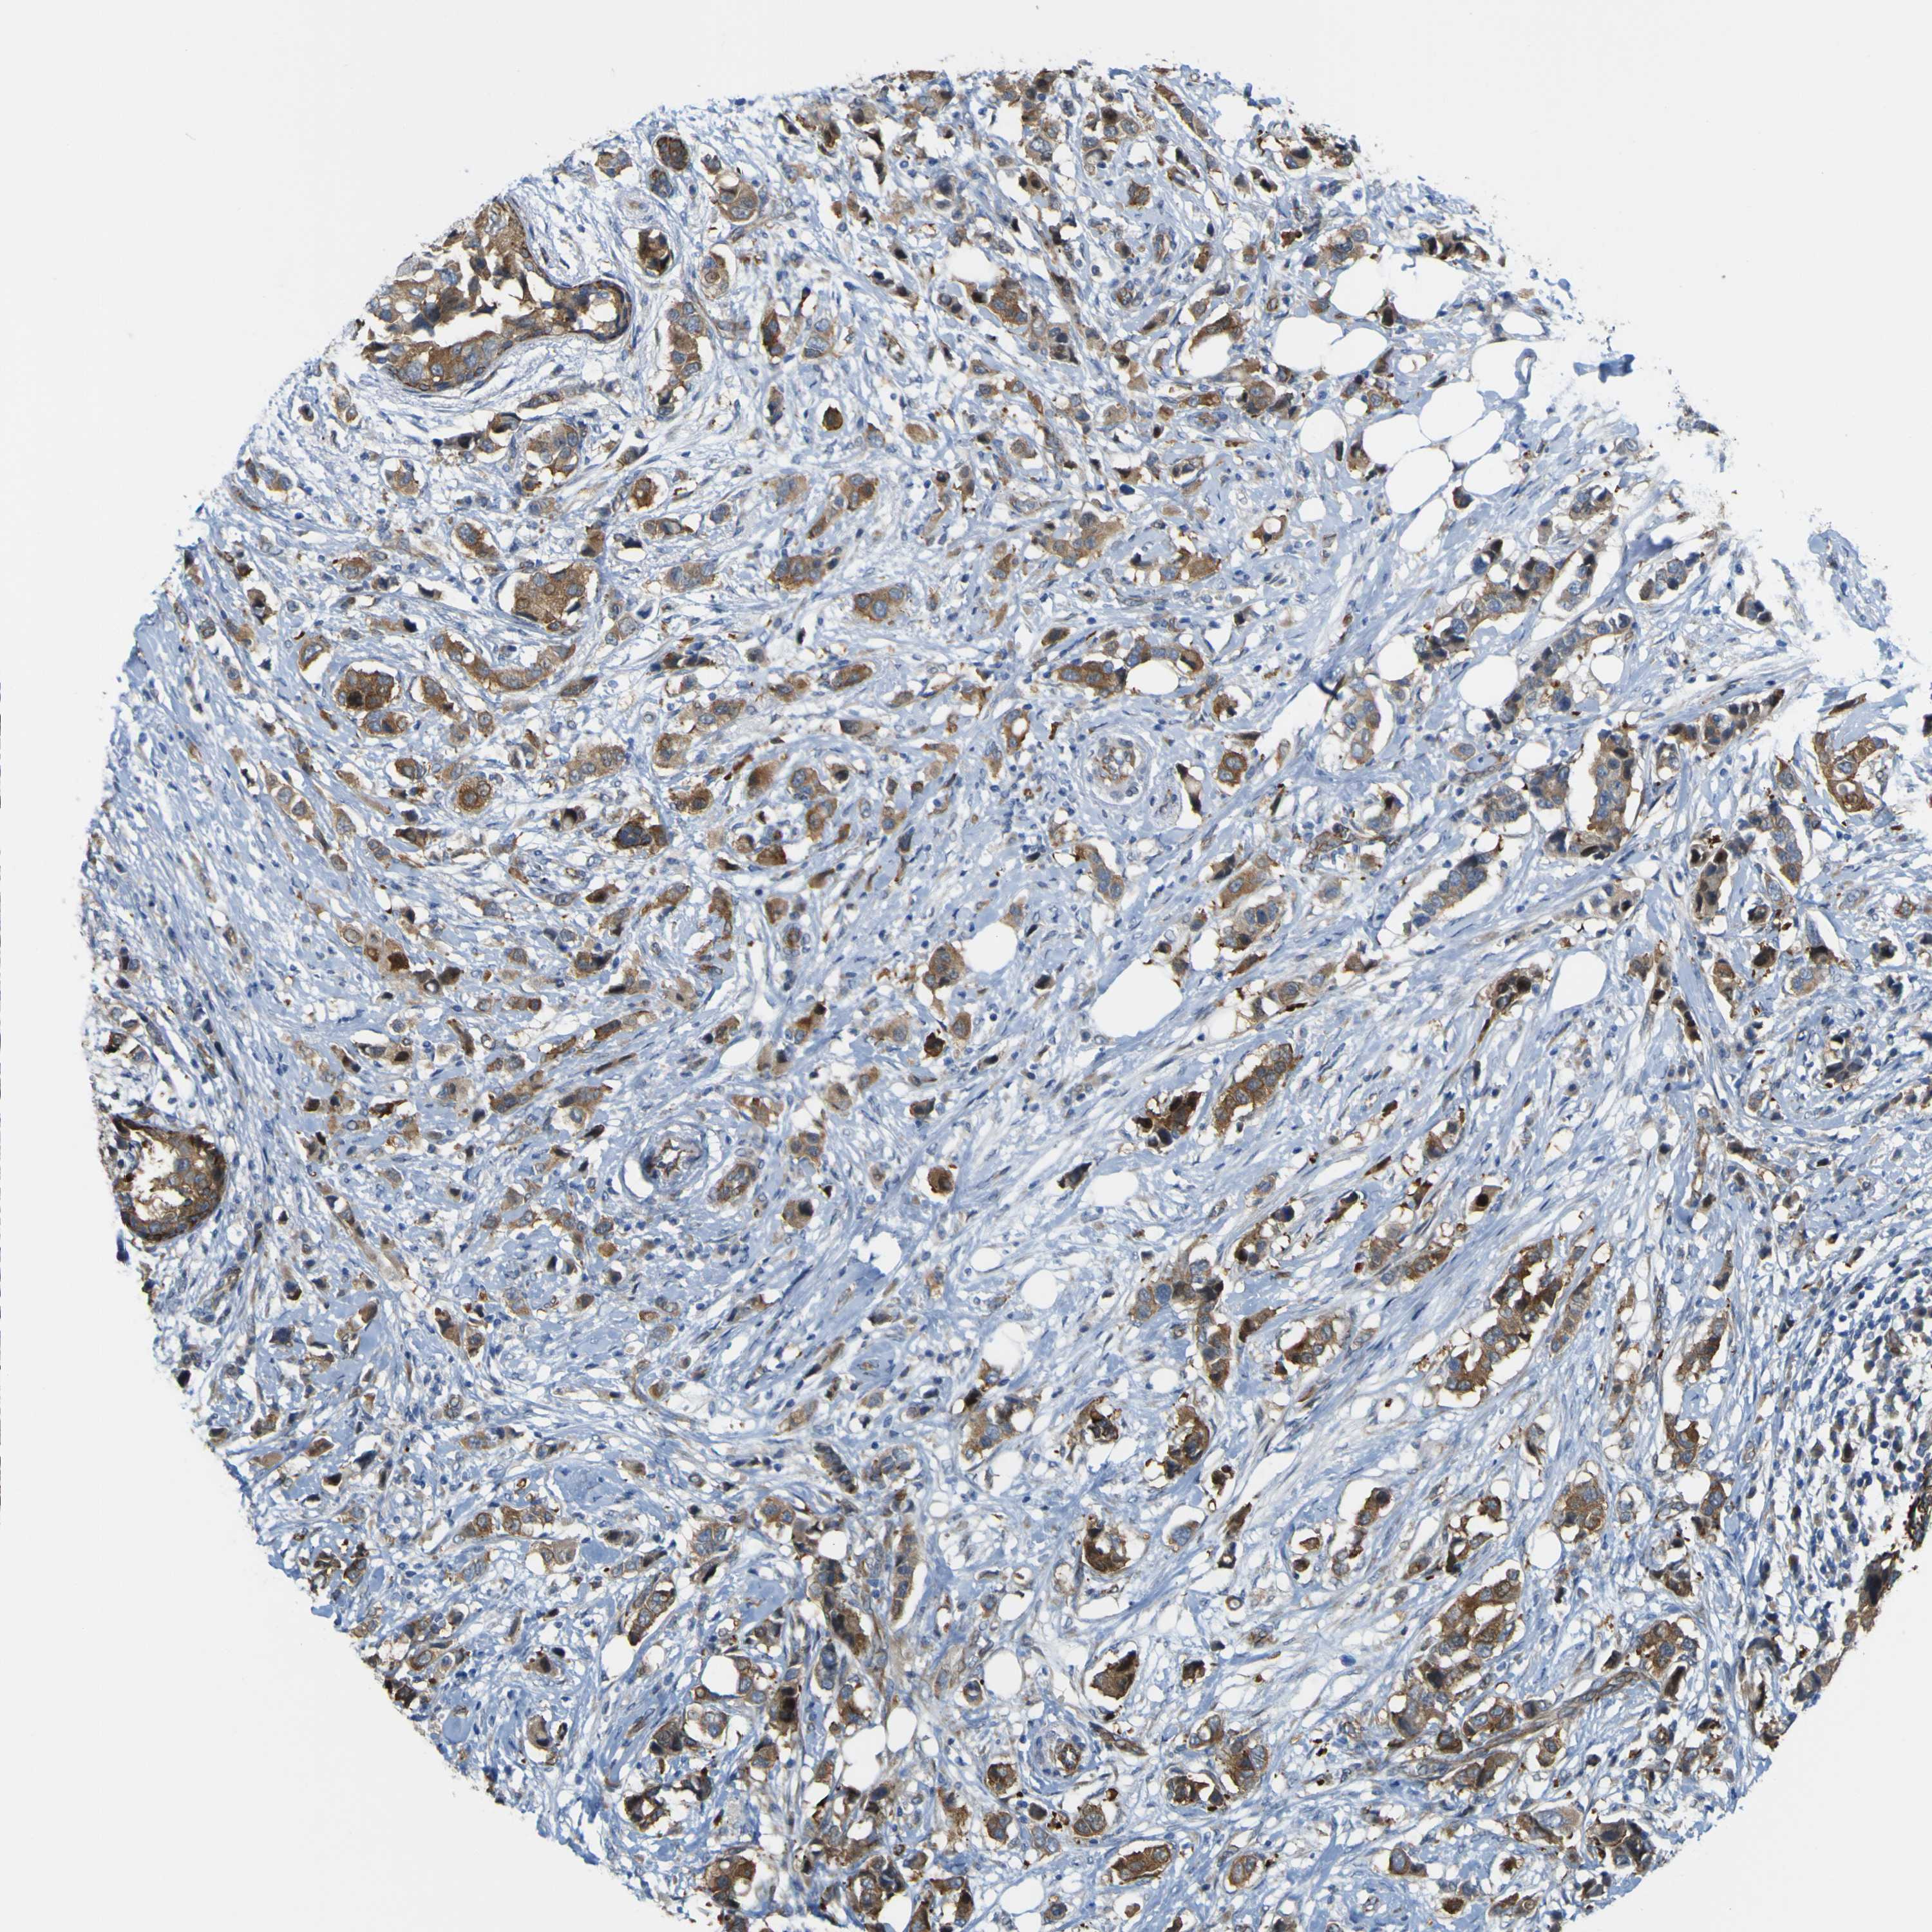

CANCER BREAST CANCER Show tissue menu

BRCA TCGA BRCA VALIDATION PROTEIN EXPRESSION